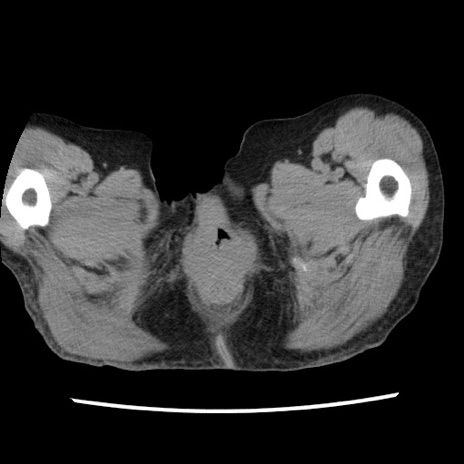

矢状断像